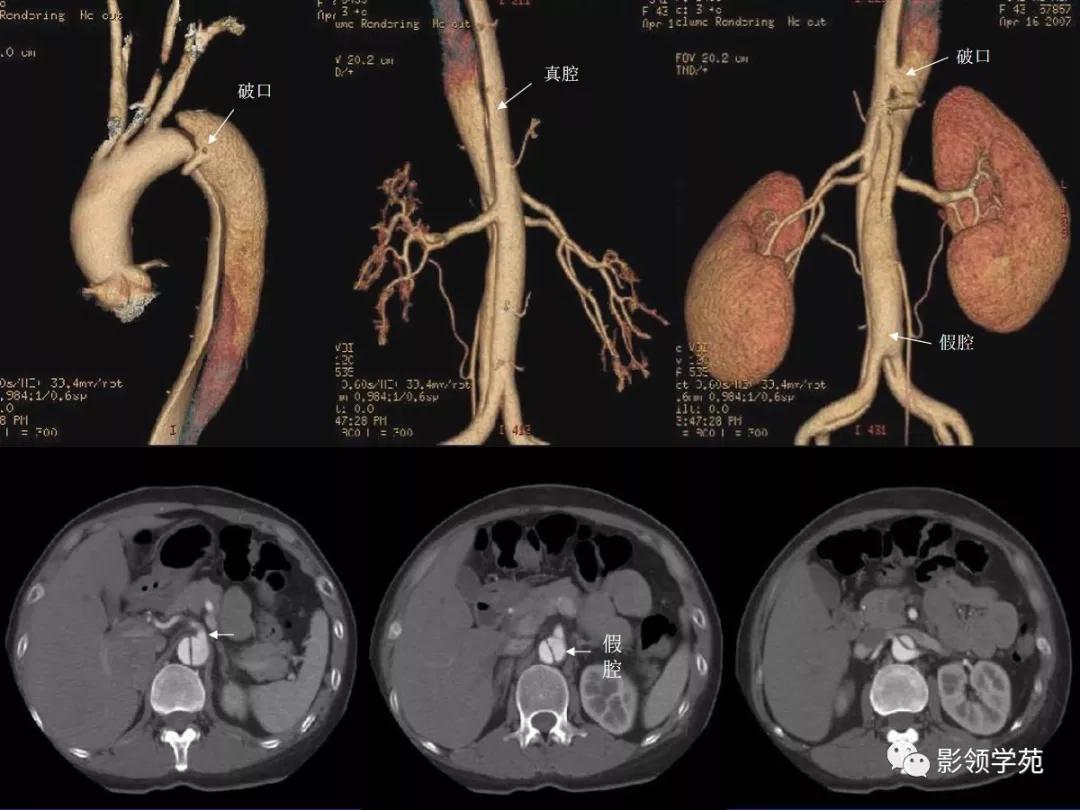

典型AD:

病理学特点:

- 内膜撕裂

- 真假“双腔” ,存在交通

- 远段同时存在再破口